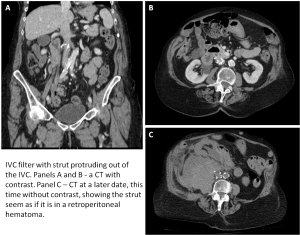

- Mal-alignment of misplacement of the filter. This is a rare complication, however, filters have been known to be misplaced terribly and there has even been a filter put into the spinal canal. Different problems are filter migration and filter penetration through the IVC walls, resulting in the filter ending up in problematic locations.

- Perforation – Sometimes, an IVC filter may perforate through the inferior vena cava into adjacent structures. In most cases this happens after time has elapsed from the filter insertion. This may be due to filter struts breaking or twisting or after filter migration and burrowing through the IVC wall.